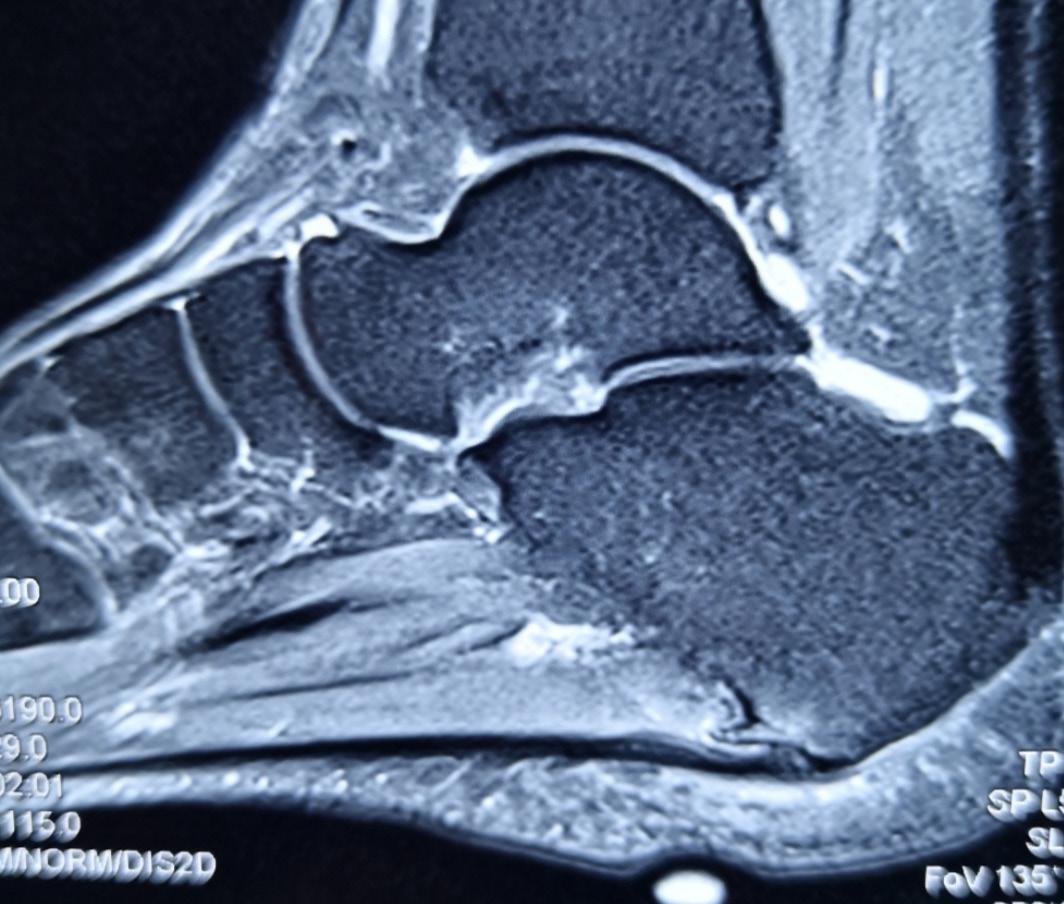

Posterior malleolar fractures (PMFs) account for up to 50% of ankle fractures when assessed with CT. The historical “one-third rule” guided fixation by fragment size; however, morphology and stability are now recognised as more important determinants of outcome.

Surgical fixation of PMFs is commonplace in unstable and displaced fracture patterns. Having spent the last decade researching PMFs, one of the most significant findings has been the importance of the correct surgical approach. Although the posterolateral (PL) approach remains common, in my practice it has been completely abandoned. Increasing evidence supports the medial posteromedial (MPM) approach in the exposure and fixation of PMFs, which has substantial benefits over the PL approach.

I will discuss these advantages of the MPM over the PL approach in the following article.

Recent CT-based studies have reported >90 % anatomical reduction within >>

2mm and >90 % syndesmotic congruity after MPM fixation, however other studies using PL approach only achieve approximately 50% anatomical reduction5, 6 Our own data has shown complication rates up to 66% following PL fixation, compared with 8% using MPM when using the Clavien-Dido classification for complications.

The MPM approach overcomes the three principal limitations of PL approach, restricted exposure, unaddressed entrapment, and vascular risk. Its direct vision of the posterior and medial tibia enables true anatomical reduction, particularly in die-punch and 2B PMFs. The ability to clear PTT entrapment prevents secondary displacement and pain. Preservation of the posterior vasculature markedly decreases complication rates. Adoption requires anatomical familiarity, but reproducibility and outcomes justify its broader implementation. In my view, due the vascular risks of the PL approach specific to a two-vessel limb, continued use of the PL approach should instigate a CT angiogram pre-surgery.

Figure 4: Intraoperative fluoroscopy and clinical images showing placement of the metalwork in a 2B fracture type, through the MPM approach in the supine position.